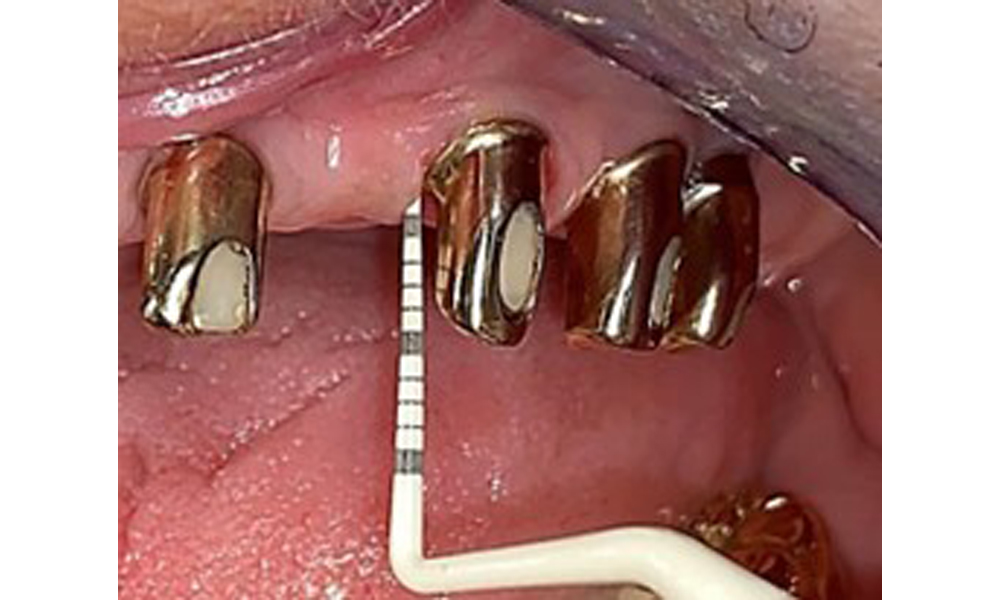

Okklusalansicht: Oberkiefer mit Zahn- und implantatgetragenen Teleskopen.

Abb. 2: Okklusalansicht: Oberkiefer mit Zahn- und implantatgetragenen Teleskopen.

Der dentale Befund stellt sich wie folgt dar: Kombinierte herausnehmbare Implantat- und zahngetragene Teleskoparbeit auf Implantaten 15, 13, 21, 23, 24, 25 und Zahn 11 (Abb. 1, Abb. 2, Abb. 3). Im Unterkiefer ist die Patientin mit einem festsitzenden Zahnersatz versorgt. 37–34 sowie 45–47 haben suffiziente Brücken (Abb. 4). Kronenränder sind intakt, aktive kariöse Läsionen sind nicht vorhanden. An Zahn 43 zeigt sich eine Compositefüllung mit Randspalt. Im Unterkiefer liegen Rezessionen mit freiliegender Wurzeloberfläche zwischen 1 – 3 mm vor. Dies trifft auch für 11 zu.

Einmal jährlich ist ein ausführlicher Parodontalstatus durchzuführen. Er dient zur umfangreichen Befunddokumentation zum Zustand des Parodonts und der Implantatsituation mit u. a. Taschentiefen, parodontaler Rezession, Furkationsbefall. So kann rechtzeitig auf eine mögliche Mucositis, Gingivitis bzw. Parodontitis oder Periimplantitis reagiert werden. Die Implantatsondierung ist mit einer Kunststoffsonde zu empfehlen. Im vorliegenden Fall zeigt das Implantat 23 mesial eine Sondierungstiefe von 4 mm. Dabei ist weder Suppuration noch Blutung festzustellen, weswegen hier keine Periimplantitis vorliegt.